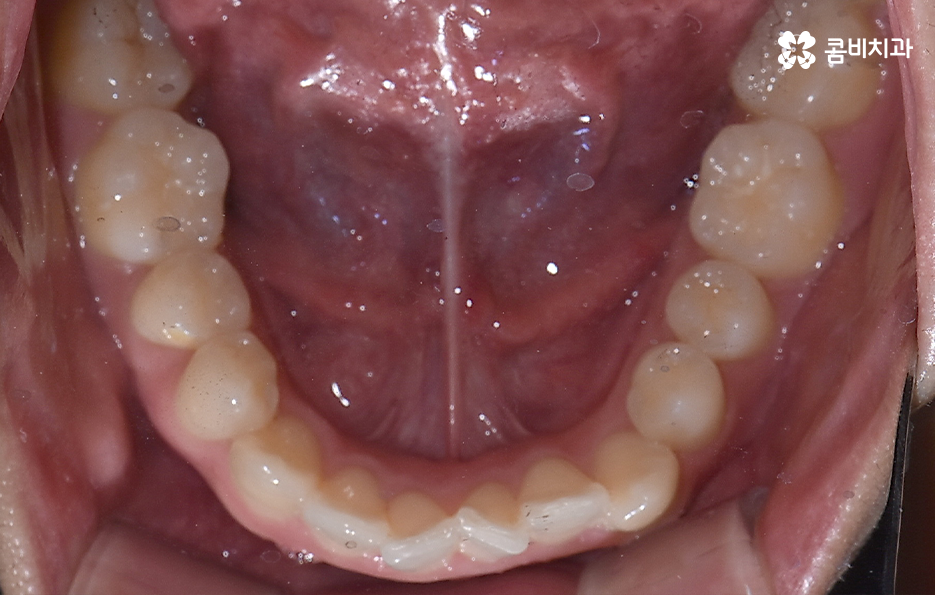

덧니가 나는 원인은 유전적인 영향부터 골격적인 부분 등 다양하지만 기본적으로는 치아가 나올 공간이 부족해서 덧니의 형태로 영구치가 자라는 경우가 많기 때문에 덧니 교정 사례에는 유독 발치 교정 사례가 많이 있는데요

요즘은 앞니만 약간 벌어져도 교정을 하는 분들이 크게 늘고 있기 때문에 덧니가 심하지 않아도 교정을 하는 분들도 많기 때문에 덧니 교정 사례에서도 비발치 사례도 많지만 보편적으로 덧니 발치교정 사례가 많은 것도 사실이기 때문에 어떠한 경우에는 발치교정이 필요하며 또한 어떻게 치아교정 계획을 세우는 것이 좋을지 오늘 포스팅에서 알아볼 거예요

다만 덧니 교정 사례에서 발치교정 사례가 많은 이유는 턱뼈가 좁아서 치아가 덧니로 자란 경우가 많기 때문에 치열을 재배열하기 위해서는 치아가 움직일 수 있는 충분한 이동공간이 필요하기 때문에 공간 확보의 목적으로서 작은 어금니 양옆, 위아래 4개를 발치를 하는 발치교정법이 보편적으로 많이 활용되고 있으며 치아의 이동 공간을 확보하는 방법으로는 발치 교정법 외에도 악궁확장, 어금니 후방이동, 치간삭제와 같은 비발치적인 방법도 가능하기 때문에 치아를 얼마나 이동시켜야 할지에 따라서 치료법은 개인차가 발생되고 있어요